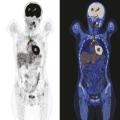

Tomographie par émission de positons : une place centrale dans le bilan et l'évaluation

La tomographie par émission de positons (TEP-scan) est une technique d’imagerie nucléaire fonctionnelle non invasive et désormais largement disponible. Elle est fondée sur l’utilisation d’un radiotraceur radio­actif ciblant un processus biologique, injecté au ­patient, dont la distribution peut ainsi ­être analysée à l’imagerie…

La démarche thérapeutique de première ligne a largement évolué ces dernières années, vers une optimisation du rapport bénéfice-risque. Que la présentation du lymphome de Hodgkin (LH) soit localisée ou avancée, le standard de traitement intègre désormais la tomographie par émission de positons (TEP) pour guider la stratégie, en…